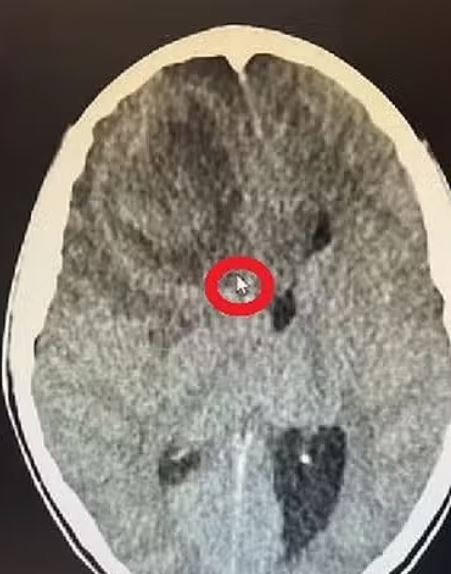

米蓮娜原本還能走路說話,誰知回家後病情急速惡化,疼痛加劇,她一度抱著頭尖叫喊痛,26日再度送醫,卻依舊被遣返。28日,米蓮娜突然在家中浴室昏倒,緊急住院隔天早上就突發心臟驟停,從此昏迷再也沒醒來。經過電腦斷層檢查,才在米蓮娜腦中發現一顆5公分腫塊,但礙於該間醫院沒有神經專科確認腫塊究竟是腫瘤、囊腫、水腫還是血塊,以致米蓮娜病況越來越糟。